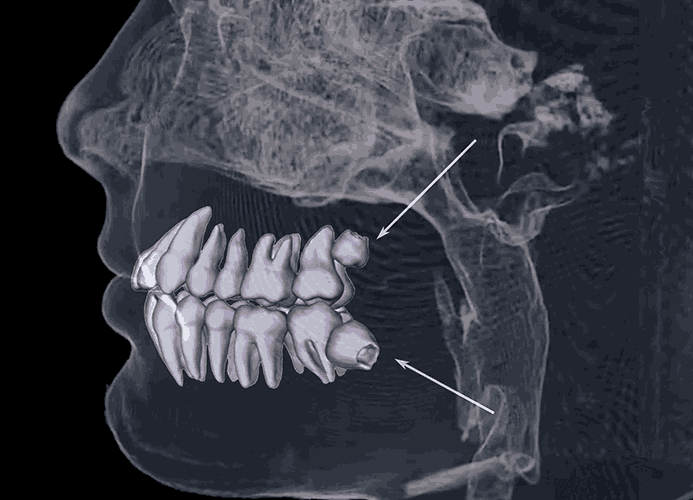

매복 사랑니 발치를 부주의하게 진행할 경우 신경손상, 상악동천공 등의 부작용이 생길 수 있습니다. 청담뷰는 사전에 파라노마 방사선과 3D-CT(컴퓨터단층촬영)검진을 통해 신경손상 없이 안전하게 발치해 드리며 최소한의 통증으로 안전하고 신속하게 사랑니 수술을 받을 수 있습니다.

사랑니 발치는 정확한 진단과 위치 파악이 중요합니다.

사랑니 발치의 정확한 진단과 발치를 위해 CT촬영을 통한 정밀 진단 후 수술을 받는 것이 안전합니다.